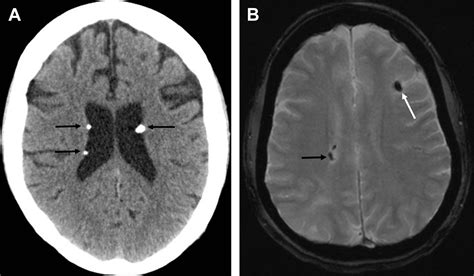

The hallmark brain lesions in Tuberous Sclerosis Radiology include:

• Cortical Tubers: These are areas of cortical dysplasia, appearing as hyperintense signals on T2-weighted and FLAIR MRI images. They are most commonly found in the frontal lobes.

• Subependymal Nodules (SENs): Small, benign nodules located along the walls of the lateral ventricles. They are often calcified and can be easily visualized on both CT and MRI scans.

• Subependymal Giant Cell Astrocytomas (SEGAs): These are tumors that typically arise from SENs near the foramen of Monro. Unlike static nodules, SEGAs have the potential for growth and can cause obstructive hydrocephalus, requiring urgent surgical or pharmacological intervention.

• White Matter Radial Migration Lines: These appear as linear bands of hyperintensity extending from the periventricular region toward the cortex, representing disrupted neuronal migration.